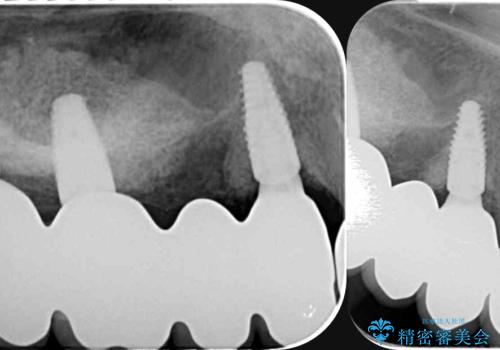

全体的な歯周病検査を行い、多数の残すことのできない抜歯の必要な歯を認めたため、残せる歯に対しての徹底的な歯周病治療、失った歯に対しブリッジ・インプラント治療を全顎的に行っていくこととしました。

長期間にわたる治療後、歯に対する意識も大きく変わりプラークコントロールも非常に良くなりました。

数ヶ月に一度のチェックをしっかりと行い、ブリッジ・インプラントが長期間使用できるようメンテンスを行っていきます。